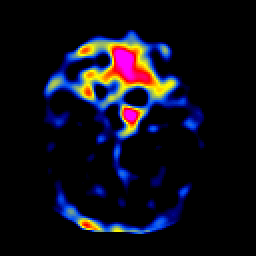

SPECT TL Study #1 -- Slice #15

[Home][Help][Clinical][Tour 1][Tour 2][Tour 3] Slice 15